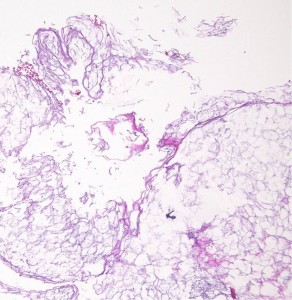

病理所見

豊富な皮脂腺 sebaceous gland を有する扁平上皮 epidermis とケラチン dry keratin material(右下)が特徴です

皮脂腺を有する扁平上皮とkeratin material (右下)の概観

皮脂腺を有するepidermisの強拡大,Keratin materialの強拡大